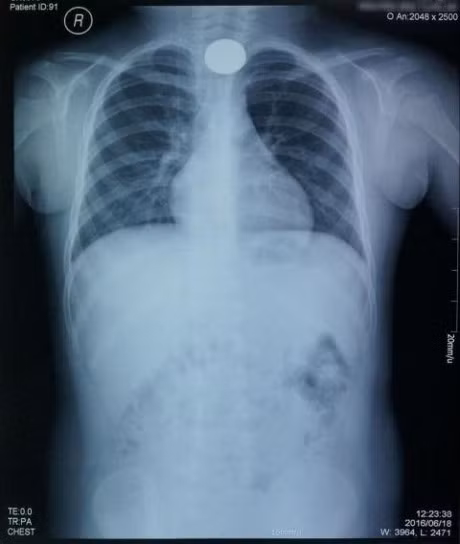

Qua kết quả X-Quang, các bác sĩ tại khoa Liên chuyên khoa xác định có dị vật mắc ở vị trí vùng cổ của bé, bịt đường thở gây nguy hiểm tính mạng.

Đồng xu nằm trong cổ bé trai, bít đường thở.

Ngay lập tức, bé N. được chuyển đến Trung tâm Nội soi của bệnh viện để thực hiện nội soi cấp cứu có tiền mê. Các bác sĩ đã nhanh chóng kiểm tra thấy dị vật là đồng xu chơi game, kích thước khoảng 2.5cm, mắc ở 1/3 trên thực quản cổ của bé trai. Tiến hành cấp cứu, các bác sĩ đã gắp đồng xu ra bằng dụng cụ chuyên dụng.